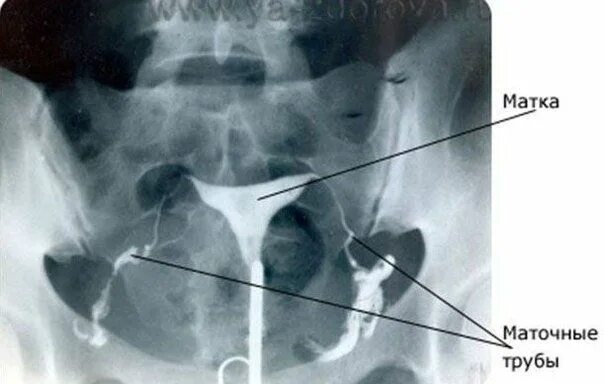

Что значит маточные трубы не визуализируются